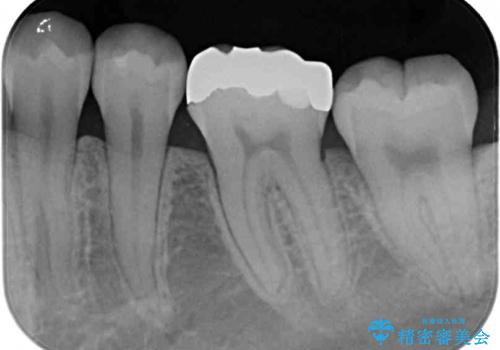

- 下の奥歯(右下7・左下7)にあって目立ってしまう銀歯を白くしたいとのことで来院された患者様です。

セラミックインレーにて修復治療を行うこととしました。